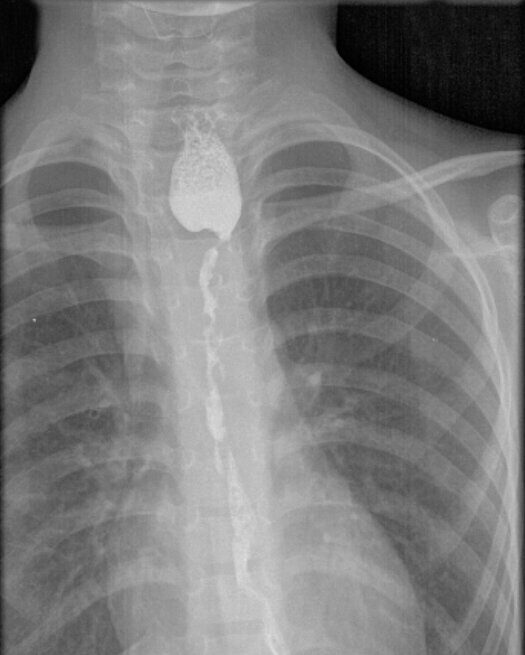

Сложнейшую операцию - колоэзофагопластику - провели хирурги Ивано-Матренинской детской клинической больницы. Уже сейчас можно с уверенностью сказать, что оперативное лечение помогло 8-летнему ребенку вернуться к нормальной полноценной жизни.

Колоэзофагопластика — вид реконструктивного оперативного вмешательства, при котором из тканей толстой кишки создается искусственный пищевод.

- Сейчас у этого пациента все хорошо, и я очень рад, - говорит заведующий оперблоком Ивано-Матренинской детской клинической больницы, врач детский хирург Вячеслав Хамзиевич Латыпов. – Четыре года назад мальчик поступил в больницу с острым случайным бытовым отравлением щелочью, которое привело к рубцеванию пищевода. Это потребовало длительного курса бужирования. Но, к сожалению, вмешательство не оказало нужного эффекта. Поэтому мы с коллегами приняли решение провести оперативное лечение – колоэзофагопластику. На сегодняшний день уже можно с уверенностью сказать, что операция прошла успешно. Ребенок ест сам, ест хорошо, цель операции достигнута.